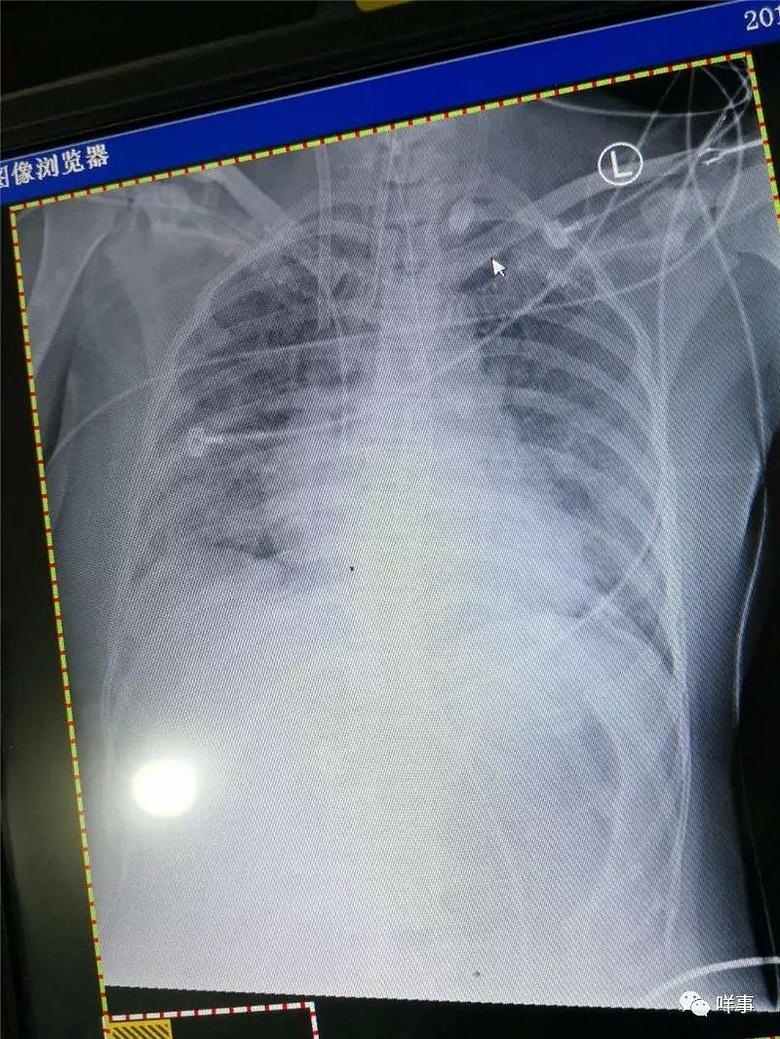

广州夫妇患流感花几十万 一场感冒险致命 1月31日感冒起病,2月4日看了次普通门诊,到2月5日入院、住ICU,2

对于很多人来讲,感冒吃药,一周的时间也就不过广州一位37岁的女患者李云的一场流感,已经花了十几万了。

广州夫妇患流感花几十万怎么回事?为什么广州夫妇患流感花几十万?(4),第14天,情况好转;第18天,评估撤离

第14天,情况好转;第18天,评估撤离ECMO机后双肺能够支撑生命需要。在向沈卫介绍病情时,高友山乐观的和被